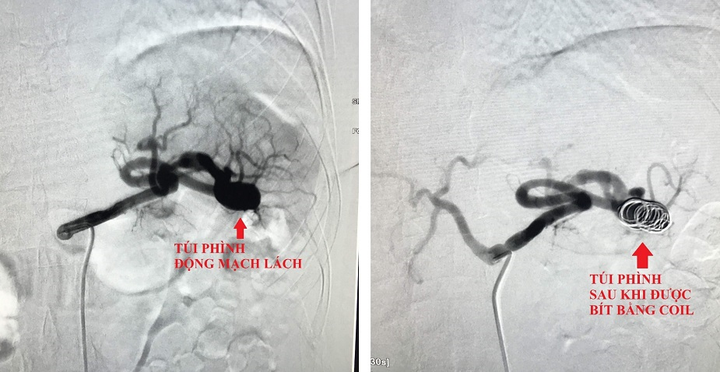

Hình ảnh chụp của máy DSA túi phình động mạch lách trước và sau khi được bit. (Ảnh: BSCC)

Tại khoa Tim mạch 1, bác sĩ tiến hành siêu âm bụng và mạch máu phát hiện túi phình mạch máu bất thường ở gần lách. Ê-kíp chỉ định chụp cắt lớp vi tính có bơm thuốc cản quang và xác định túi phình ở động mạch lách. Túi phình có nguy cơ vỡ bất cứ lúc nào đe dọa tính mạng bệnh nhân.

Sau khi hội chẩn, bác sĩ tiến hành can thiệp bằng ống thông qua đường mạch máu nhằm tránh nguy cơ phẫu thuật phải cắt lách.